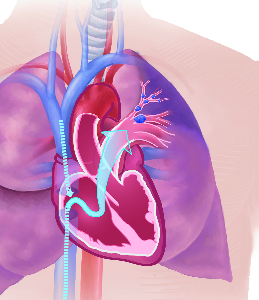

Über 860 Stichworte mit 120 Illustrationen auf 400 Seiten machen aus dem Lexikon der Lunge ein

wertvolles Werk.

Detailreiche Fotografien aus der medizinischen Praxis ergänzen die Texte; moderne, genaue,

wissenschaftliche Zeichnungen geben Einblick in die Anatomie und die Funktion der Lunge und

anderer Organe.